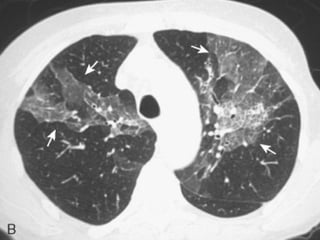

 TCAR

 Extensão do acometimento pulmonar e fase da

dça.

▪ Precoce: áreas em vidro fosco

▪ Avançada: faveolamento

 Padrão definitivo – Todos os 4 critérios são

necessários:

 Predominância nas bases e regiões subpleurais;

 Anormalidades reticulares;

 Faveolamento com ou sem bronquiectasias de

tração;

 Ausência de todos os 7 critérios inconsistentes

com o padrão de UIP